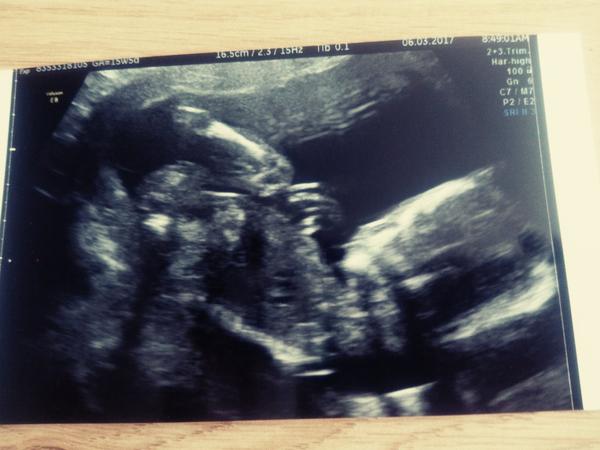

@luta13 ahooooooj 🙂 zatiaľ som pribrala len kilo 🤰 bruško rastie cítim už aj jemné pohyby je to niečo krásne ❤ držíme sa dobre máme už aj mená vybrané pre dievčatko Vivien a pre chlapčeka Mateo 😎 v pondelok 13.3. mi uz povedia čo to bude veľmi sa teším aj na to že bábätko znovu uvidím 👶 ďakujem veľmi pekne že namna myslíš v pondelok dám vedieť ❤

@nataliaondrejkova mate to tam...fuuuu